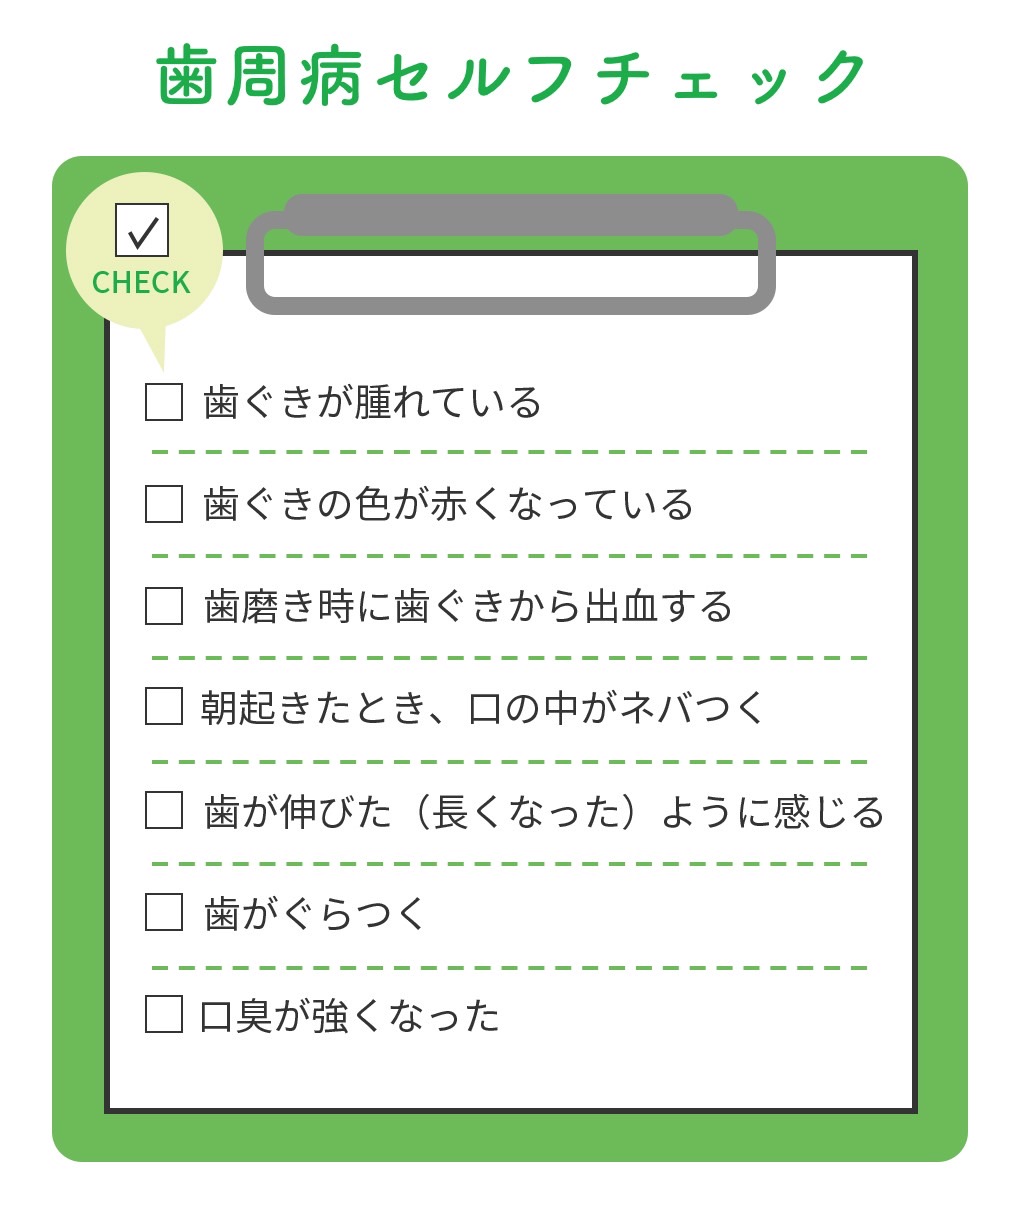

About歯周病とは

歯周病は、歯肉や歯を支える骨など、歯の周りの組織に炎症を引き起こす感染症です。

歯周病が進行すると、歯ぐきだけでなく、歯を支える骨まで溶けてしまい、歯がぐらつくようになり、最終的には抜歯が必要となる場合もあります。さらに、歯周病は初期段階では自覚症状がほとんどなく、発見が遅れがちです。

歯周病が進行して歯ぐきが下がったり、骨が溶けてしまった場合、現代の医療技術でも完全に元の状態に戻すことは難しくなります。だからこそ、定期的な検診やセルフチェックを行い、早期発見・早期治療を心がけることが非常に重要です。

歯周病は、初期の段階ではほとんど自覚症状がないまま進行してしまうため、気づいたときにはすでに重度になっていることも少なくありません。進行の程度によって治療法や回復の可能性が大きく異なるため、自分の状態を知ることがとても大切です。